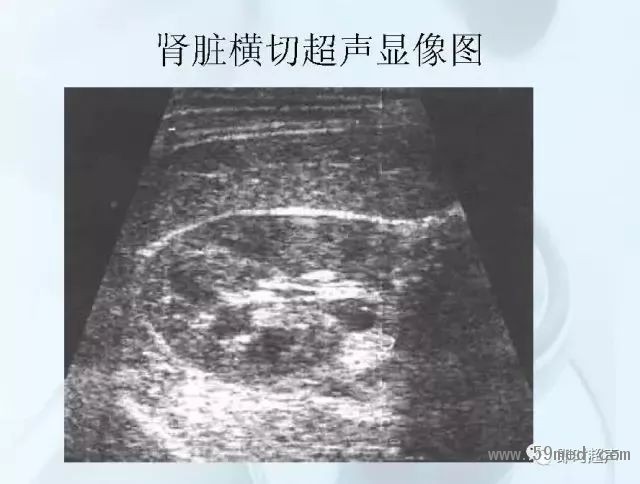

新聞中心 收藏!正常B超解剖圖譜,超實用!